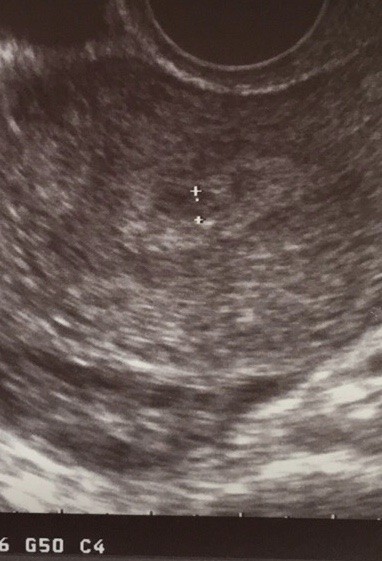

Dziewczyny ja dzisiaj po wizycie u lekarza 😀 dosyć wcześnie ale moja chciała mnie zobaczyć bo naprawdę można powiedzieć ze trochę cud 😀 dzisiaj beta 603 progesteron 40 ale dalej mam brać luteinę. Zrobiła mi usg żeby zobaczyć czy może już coś będzie widać bo u mnie 4+2 i coś zaczyna się dziać w macicy😀

0F831BBD-FA8C-4DC4-9C6A-104A4BA11013.jpeg